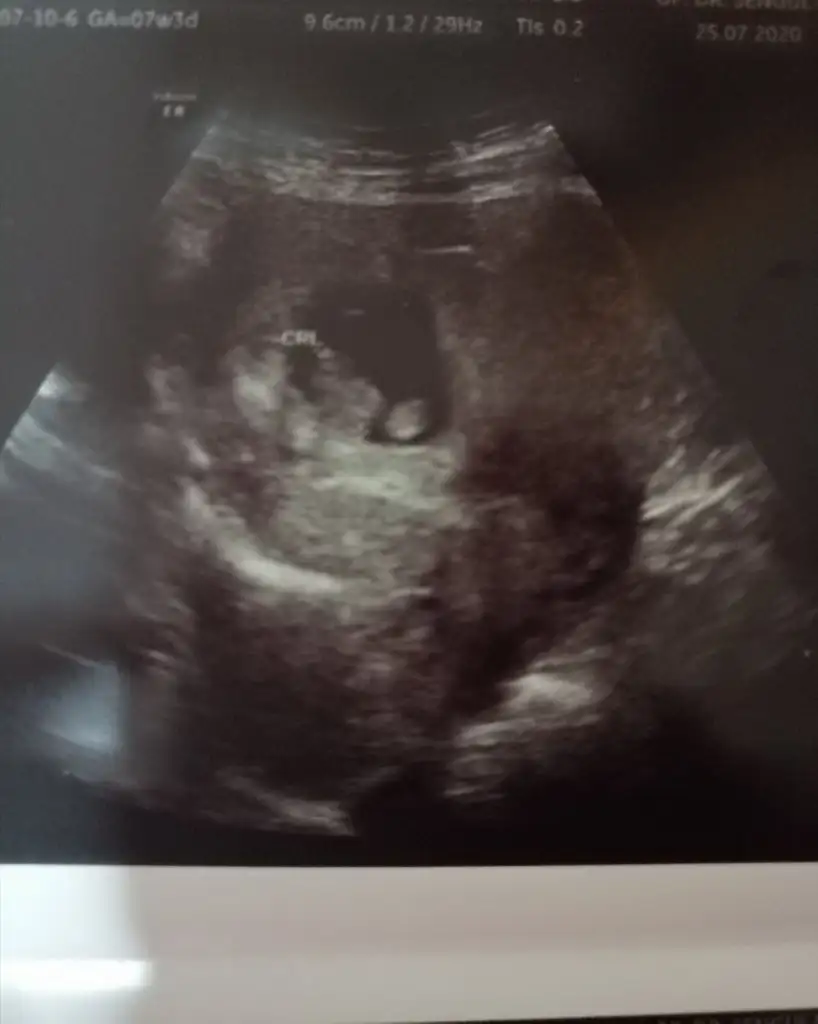

Eki Görüntüle 473837

bu benim kizim cikinti gayet net ve ortada ve ben kizim diyooo